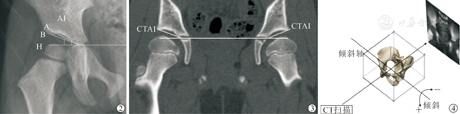

调阅患儿CT影像资料并导入CT后处理工作站,输入重建命令生成骨盆三维重建图像,包括多平面重建(MPR),容积再现技术(VRT)。调整三维重建模型至标准中立位,即满足左右两侧闭孔横径相等,两侧髂前上棘与耻骨联合所形成的前骨盆平面与扫描台面平行;在工作站内将中立位的三维模型生成DRR图像。在DRR图像上,我们定义髋臼外上缘高密度弧线最外侧点为点A,通过其测量的髋臼指数为AAI,定义A点下方骨性阴影的最外上缘点为点B,通过其测量的髋臼指数为BAI(图2)。固定此时的骨盆三维模型空间位置,利用MPR技术生成其冠状位骨盆扫描图像,选择扫描平面通过该侧股骨头最大直径的MPR图像,测量其上的髋臼指数CTAI(图3)。以通过骨盆双侧Y形软骨中心点的直线为轴线,将骨盆三维模型进行前后倾斜(图4),每隔3°生成一张DRR图像,观察连续角度变化中A、B两点的位置改变,记录两点重叠时的骨盆倾斜角度。

最后纳入研究对象总共33例,年龄为(2.90±1.32)岁;其中男8例,女25例,共52髋;影像学上按照Ogata髋臼形态分型,Ⅰ/Ⅱ型共19髋,Ⅲ型23髋,Ⅳ型10髋。按照髋关节发育不良的诊断标准[8],其中26髋为正常髋关节,26髋为发育不良髋关节。对于所有髋关节,其CTAI的测量值为(28.40± 6.74)°,AAI的值为(27.98±6.51)°,而BAI的值为(24.93±5.62)°,AAI与BAI的差值为(3.06±3.06)°,范围为0~11.60°。表1显示AAI与BAI的差值在正常组髋关节与发育不良组髋关节之间差异无统计学意义(P=0.181),而在影像学分型中,各组间差异具有统计学意义(P<0.001);可见AAI与BAI的差异受到髋臼外上缘显影形态的影响,而不受髋臼发育状态的影响。CTAI与AAI之间呈高度相关(P<0.001),其两者差异未见明显统计学意义(P=0.112),CTAI与BAI之间也呈高度相关,其两者之间差异具有统计学意义(P=0.000,表2)。CTAI与AAI之间的差值为(-0.41±1.83)°。采用Bland-Altman分析检验CTAI与AAI测量的一致性,图5显示大部分的髋关节其CTAI与AAI的差值均位于其平均差值的95%可信区间以内,而有3髋其CTAI值与AAI值差异与其余髋关节相比增大,导致散点分布在CTAI与AAI平均差异的95%可信区间以外范围(图5)。